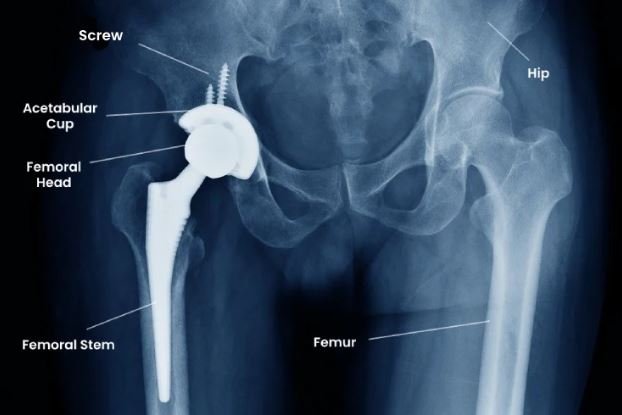

Total hip replacement involves replacing the damaged hip joint with a prosthetic implant made of metal, ceramic, or high-grade polyethylene components. The goal is to eliminate pain, restore joint alignment, and improve mobility.

Dr. Ponnanna K.M explained that modern surgical techniques aim to minimize tissue disruption while ensuring accurate implant positioning.

Dr. Ponnanna K.M highlighted that implant choice is individualized, considering patient age, activity level, and bone quality.